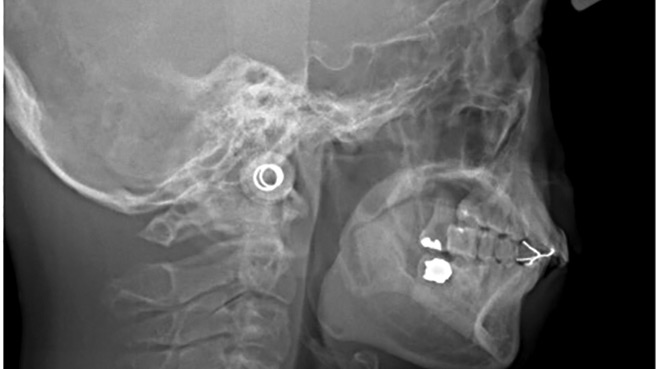

Managing Hemifacial Microsomia with Total Custom TMJ Replacement

Caminiti-Figure-4-Slide6-thumbnail alternate text for this image

Introduction: The Oral and Maxillofacial Surgery program at the University of Toronto supports the Cleft Lip Palate and Craniofacial Program at Holland Bloorview Kids Rehabilitation Hospital in numerous ways. The program’s director, residents and the Temporomandibular Joint and Orthognathic Surgery Fellows work collaboratively with staff orthodontist Dr James Noble and the chief of Dentistry, Dr. … Read more